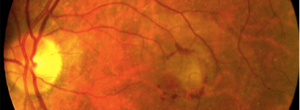

color nvc

· 16/01/2015

A delphi study to detect deficiencies and propose actions in real life treatment of neovascular age-related macular degeneration.